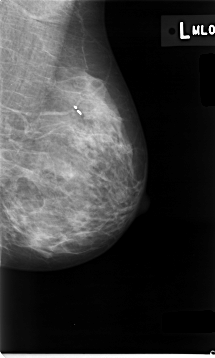

C_0008_1.LEFT_MLO

LEFT_MLO LINES 4648 PIXELS_PER_LINE 2792 BITS_PER_PIXEL 12 RESOLUTION 50 NON_OVERLAY